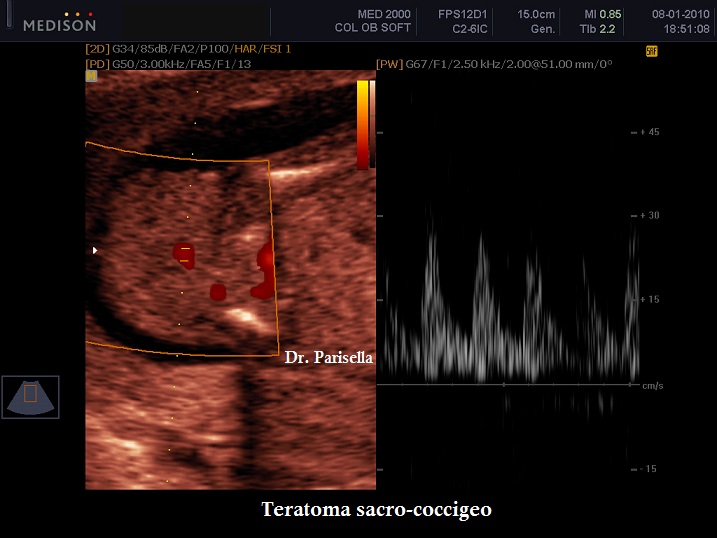

Dal punto di vista ecografico si presenta come una massa esofitica ad origine dalla regione sacrale, ad aspetto di tipo solido o complex nell'85% dei casi o di tipo cistico nel 15% dei casi; nel 35% dei casi sono presenti delle calcificazioni.

Importante è lo studio della vascolarizzazione della massa: il riscontro di una vascolarizzazione elevata è caratteristico delle masse più voluminose ed a crescita rapida, mentre una vascolarizzazione assente o modesta si riscontra nelle masse cistiche e in quelle meno voluminose ed a crescita lenta. La vascolarizzazione inoltre, può creare uno shunt ad alta gittata che a sua volta può essere responsabile dell'insorgere di un Idrope Fetale.